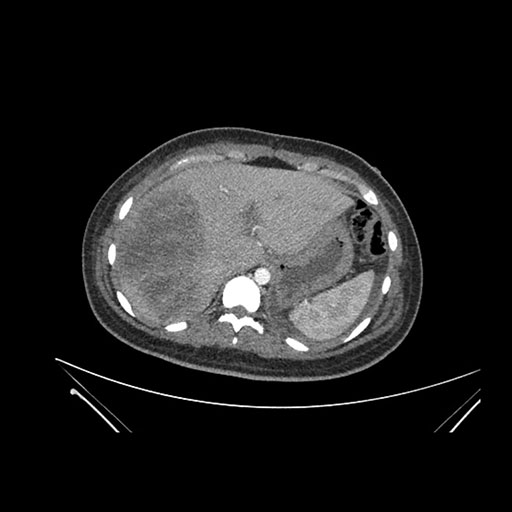

Axial Venous

Imaging analysis

Based on initial findings, which issue(s) would you be most concerned about?